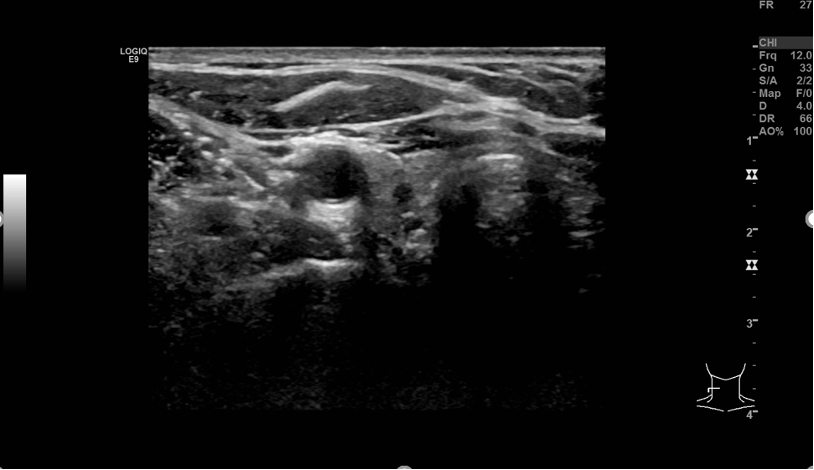

今年2月份偶然一个机会来到上海,到瑞金康复医院做甲状腺B超检查,其中提示右侧叶中极、下极,左侧叶中极结节性病灶,拟TI-RADS 4A类,建议其穿刺和基因检测。